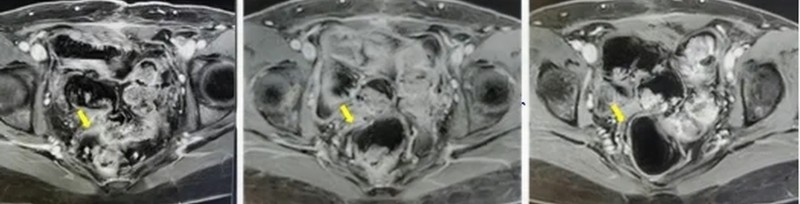

受试者接受TIL回输前、回输后6周及回输后12周影像资料

出院后,每次随访结果都带来惊喜:肿瘤标志物持续降低,肿瘤不断缩小,治疗后两个多月,各项检查指标均恢复正常。如今,4年过去,L女士早已回归正常生活和工作,无需长期服药,也不用再频繁辗转于各大医院,彻底摆脱了癌症带来的生理和心理煎熬。